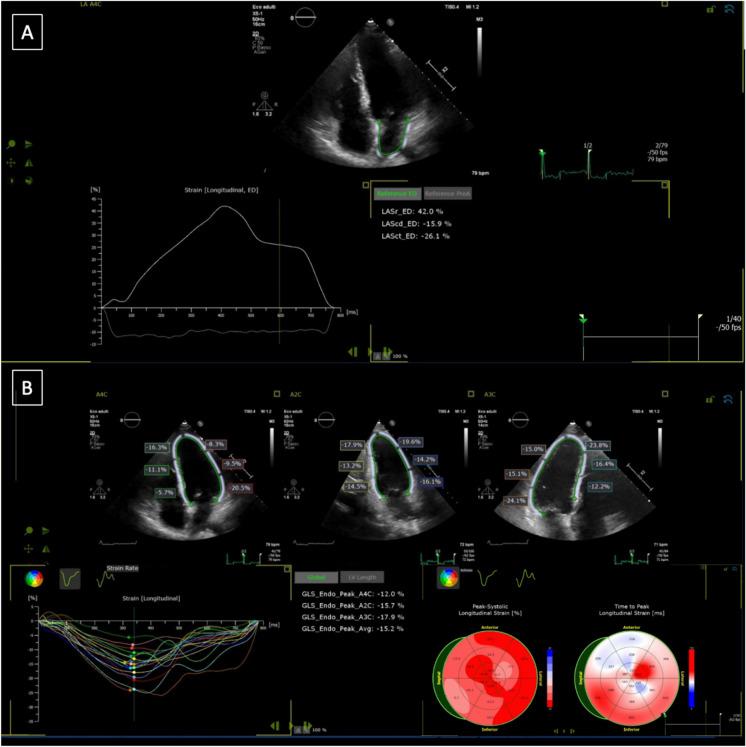

Trastuzumab is widely used in HER2 breast cancer. However, it may cause left ventricular (LV) dysfunction. A decrease in LV global longitudinal strain (GLS) has been previously demonstrated to be a good predictor of subsequent cancer therapy related dysfunction (CTRCD). Left atrial morphological remodeling during Trastuzumab therapy has also been shown. The aim of this study is exploring the relationship between early changes in left atrial function and the development of Trastuzumab-induced cardiotoxicity. Consecutive patients with diagnosis of HER2+non-metastatic breast cancer treated with Trastuzumab were prospectively enrolled. A clinical, conventional, and advanced echocardiographic assessment was performed at baseline and every three months, until a one-year follow-up was reached. One-hundred-sixteen patients completed the 12 months follow-up, 10 (9%) cases of CTRCD were observed, all after the sixth month. GLS and LVEF significantly decreased in the CTRCD group at 6 months of follow-up, with an earlier (3 months) significant worsening in left atrial morpho-functional parameters. Systolic blood pressure, early peak atrial longitudinal strain (PALS), peak atrial contraction (PACS) and left atrial volume (LAVI) changes resulted independent predictors of CTRCD at multivariable logistic regression analysis. Moreover, early changes in PALS and PACS resulted good predictors of CTRCD development (AUC 0.85; p = 0.008, p < 0.001 and 0.77; p = 0.008, respectively). This prospective study emphasizes that the decline in PALS and PACS among trastuzumab-treated patients could possibly increase the accuracy in identifying future CTRCD in non-metastatic HER2 breast cancer cases, adding predictive value to conventional echocardiographic assessment.

曲妥珠单抗广泛用于 HER2 阳性乳腺癌。然而,它可能导致左心室(LV)功能障碍。先前已经证明 LV 整体纵向应变(GLS)的降低是随后癌症治疗相关功能障碍(CTRCD)的良好预测指标。曲妥珠单抗治疗期间左心房形态重塑也已得到证实。本研究旨在探讨左心房功能早期变化与曲妥珠单抗诱导的心脏毒性发展之间的关系。连续入组接受曲妥珠单抗治疗的 HER2+非转移性乳腺癌患者。在基线和每 3 个月进行临床、常规和高级超声心动图评估,直至达到 1 年随访。116 例患者完成了 12 个月的随访,观察到 10 例(9%)CTRCD,均发生在第 6 个月后。在 6 个月的随访中,CTRCD 组的 GLS 和 LVEF 显著降低,左心房形态功能参数更早(3 个月)出现显著恶化。多变量逻辑回归分析显示,收缩压、早期峰值心房纵向应变(PALS)、峰值心房收缩(PACS)和左心房容积(LAVI)变化是 CTRCD 的独立预测因子。此外,PALS 和 PACS 的早期变化是 CTRCD 发展的良好预测因子(AUC 0.85;p=0.008,p<0.001 和 0.77;p=0.008,分别)。这项前瞻性研究强调,曲妥珠单抗治疗患者中 PALS 和 PACS 的下降可能会提高识别非转移性 HER2 乳腺癌患者未来 CTRCD 的准确性,为常规超声心动图评估增加预测价值。